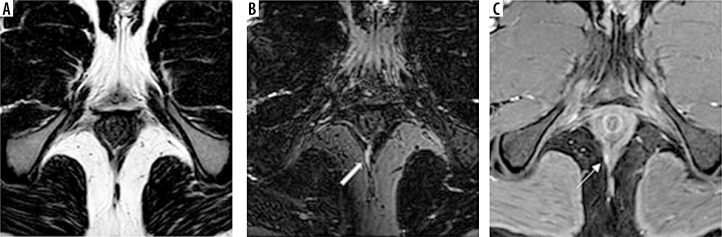

目的:肛瘘的诊断对外科医生来说是一个挑战。众所周知,磁共振成像(MRI)在其中起着重要作用。与二维(2D)序列相比,新的三维MRI序列VISTA(体积同位素涡轮自旋回波采集)可以改善肛周瘘的检测和表征。本研究的目的是通过对比增强(CE) 3D T1序列THRIVE (T1加权高分辨率各向同性体积检查)作为参考标准,比较新的3D MRI序列VISTA与广泛常规使用的T2 FSE脉冲序列在描述和表征肛周瘘方面的诊断性能。材料和方法:40名成年患者被纳入这项前瞻性研究。他们接受了常规T2 TSE和CE 3D T1 THRIVE序列的MRI肛周检查,并添加了新的3D MRI序列VISTA。T2、3D VISTA和(CE) 3D T1序列THRIVE影像分别由两名放射科医师评估,用于检测和表征肛周瘘,然后以(CE) 3D T1序列THRIVE作为参考,比较T2和3D VISTA序列。每个序列的敏感性、特异性和准确性由两名读取器计算。结果:阅读器1对3D VISTA的敏感性、特异性和准确性分别为92.5%、90.5%和93.6%,对T2 FSE的敏感性、特异性和准确性分别为84.1%、83.7%和87.3%。阅读器2对3D VISTA的敏感性、特异性和准确性分别为91.5%、92.8%和94.8%,对T2 FSE的敏感性、特异性和准确性分别为82.9%、84.5%和86.7%。结论:以CE 3D T1序列THRIVE为参照标准,与常规使用T2 FSE序列相比,肛周区3D VISTA脉冲序列在检测和表征肛周瘘方面具有更好的诊断性能。

Purpose: Diagnosis of perianal fistula represents a challenge for surgeons. It is well known that magnetic resonance imaging (MRI) plays an important role in that. The new 3D MRI sequence VISTA (Volume ISotopic Turbo spin echo Acquisition) can improve detection and characterization of perianal fistula compared with two-dimensional (2D) sequences. The aim of the study was to compare the diagnostic performance of the new 3D MRI sequence VISTA with the widely routinely used T2 FSE pulse sequence in depiction and characterization of perianal fistula by using the contrast-enhanced (CE) 3D T1 sequence THRIVE (T1-weighted high-resolution isotropic volume examination) as a reference standard.

Material and methods: Forty adult patients were enrolled in this prospective study. They underwent MRI perianal region examination using routine T2 TSE and CE 3D T1 sequence THRIVE with addition of the new 3D MRI sequence VISTA. T2, 3D VISTA and (CE) 3D T1 sequence THRIVE images were evaluated by two radiologists separately for detection and characterization of perianal fistula, then comparison between of T2 and 3D VISTA sequences was done using (CE) 3D T1 sequence THRIVE as a reference. Each sequence sensitivity, specificity and accuracy were calculated by both readers.